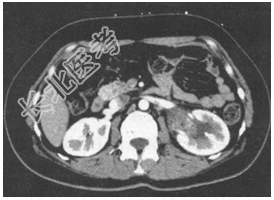

- [材料题] 患者男性,71岁,因“血尿1个月”就诊。患者于1个月前,无明显诱因出现无痛性全程肉眼血尿,无尿频、尿急,无排尿费力等不适。遂至门诊就诊。尿常规检查:尿隐血(+++)。CT检查图像见图13。

- 简答题1、该患者诊断首先应考虑

- 简答题2、患者尿脱落细胞学检查发现癌细胞。膀胱镜检查:膀胱内黏膜光整,血管纹理清晰,未见新生物,右侧输尿管喷尿清,左侧上尿路出血。予以行左侧肾盂癌根治术。术后病理检查:提示左肾盂移行细胞癌Ⅱ级,肿瘤肌层侵犯,部分区域侵及肾实质及肾盂周围脂肪,自检肾周淋巴结4枚,未见癌转移。该患者病理分期是